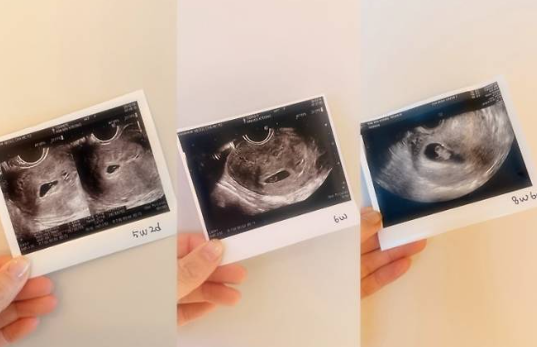

현재 임신 약 14주 차로 안정기에 접어든 상태이며,

초음파 사진과 임신 테스트기를 함께 공개해 많은 이들의 축하를 받았습니다.